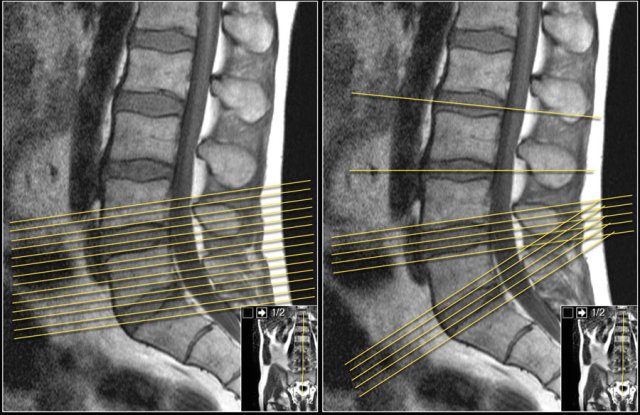

It is better to have continuous slices with the same angulation parallel to the level where nerve compression is suspected.

This has the advantage, that you can follow the involved nerve along the four levels of possible compression.

When you examine multiple levels with different angulation like in the example on the right, you will not be able to follow the whole nerve tract and you will not get the whole picture.